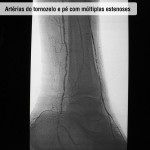

Doença obstrutiva em diabéticos